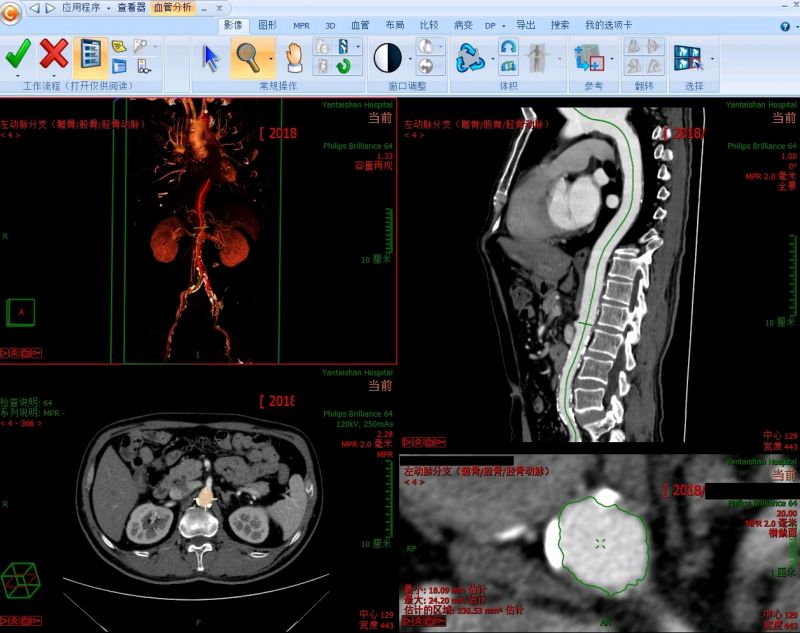

系统强大的图像处理功能为诊断医师和临床医师提供更详尽的诊断信息。作为医疗影像领域的佼佼者,锐珂PACS和RIS系统是锐珂医疗公司应用在医院信息化建设推广中功能最强大、具有革命性的产品,除加强实时3D功能和更多的交互MPR功能外,还有自动血管分析和最大/最小密度投影等功能,并可以设置为快捷键,一键转换。诊断医师在书写报告的过程中可以实时对各种图像以“关键图像”保存并提供给临床医生查看,为临床提供更多详尽的信息,为患者提供更加优质的服务。